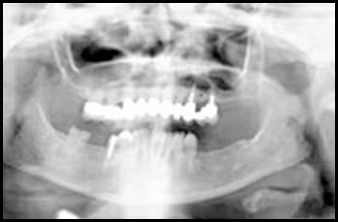

These figures demonstrate the effects of twisting. Elongation of left mandible, reduction in size of teeth on the opposite side, occlusal plane canting and pronounced tooth overlap on the same side.

Figure 43A. Panoramic Image.

Figure 43B. Panoramic Schematic.